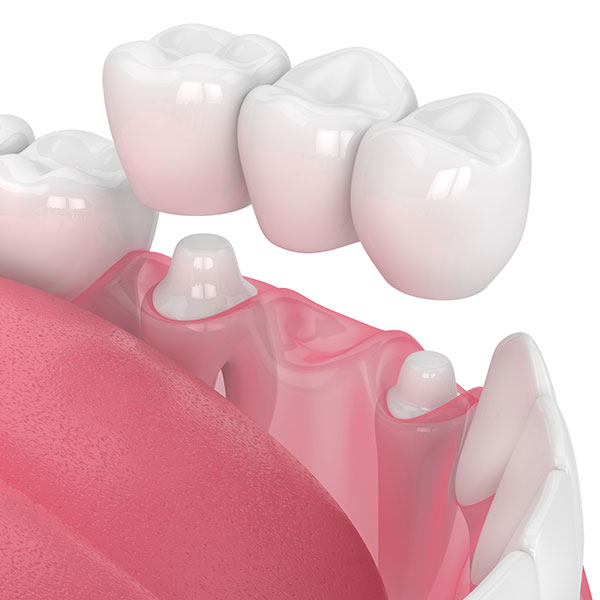

抜歯した周りの歯を削ります。型取りをして、次の回にブリッジをセメントで合着します。

ブリッジを一言で表現するなら『保険で固いものが食べれるけど歯に1番悪い』

後述する入れ歯と比べると食事のストレスはかなり少ないので、そこは大きなメリットです。

ただし、逆に言えばメリットはそれくらいです。歯を他治療と比べてダントツで削るので当然歯には良くないです。

あとは設計にもよりますが例えば2本の歯で3本分の咬む力を支えることになるので、当然負担が大きくかかります。ダミーの歯の部分は、スーパーフロスという専用の器具を用いてお掃除してもらうのですが、これがなかなかに面倒です。ちゃんとやらないと、むし歯や歯周病リスクが上がってしまいます。基本的には抜歯した周りに歯があることがブリッジ治療の条件なので、多数歯がない場合などは適用外となります。